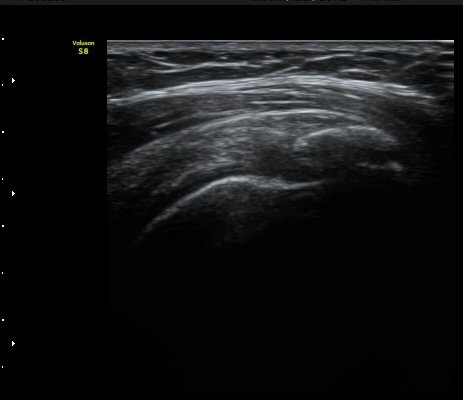

±Ø»ó°Ç Á¾´Ü¸é°Ë»ç½Ã ±Ø»ó°ÇÀÇ Ç¥Ãþ¿¡¼­ °üÂûµÇ´Â °ßºÀ¿À±¸µ¹±â Ⱦ´Ü¸é°Ë»ç»ó¿¡¼­

ÀδëÀÇ ºñÈİ¡ °üÂûµÈ´Ù(»çÁø 4). ±Ø»ê°ÇÀÇ Á¾´Ü¸é°Ë»ç¿Í Ⱦ´Ü¸é°Ë»ç¿¡¼­ ±Ø»ê°Ç ½ÉÃþ¿¡

Àú¿¡ÄÚ º´º¯ÀÌ °üÂûµÈ´Ù(»çÁø 5, 6).